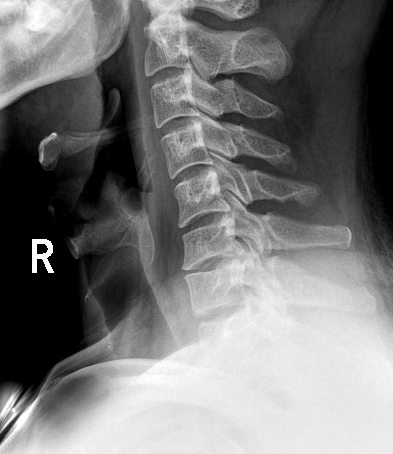

临床图像